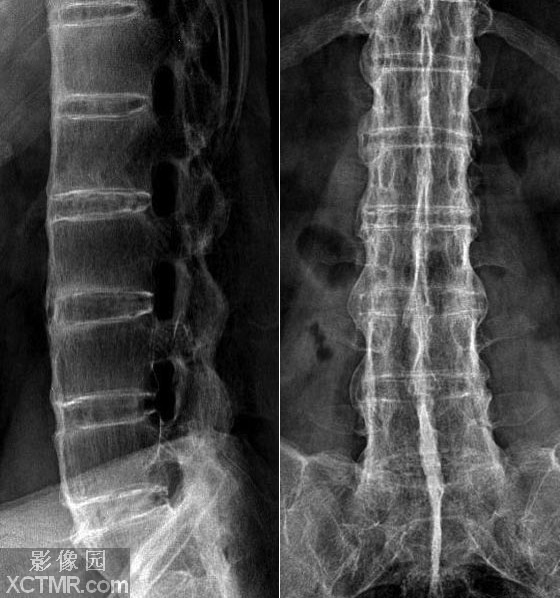

QZ16030094 姓名:陈先生 性别:男 年龄:32岁

- 病情

AS ①晚期 ②重度 病史:5年+

- 治疗

治疗后骶髂关节疼痛消失,腰椎前屈、背伸侧弯活动自如,膝关节无压痛感,复查血沉、C反应蛋白、等各项检查均已达到临床康复的标准。